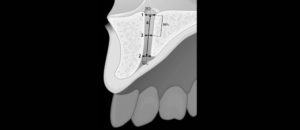

La utilización de la tomografía computarizada de haz cónico (TCHC) en la planificación de implantes dentales ha sido desde sus inicios muy controvertida, la Asociación